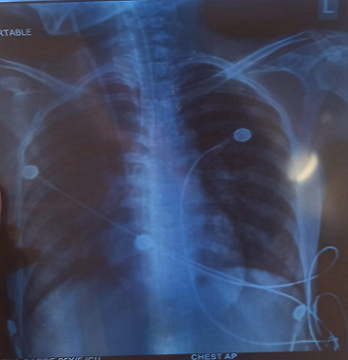

Figure 3 : Chest X-ray (PA view) showing bilateral patchy heterogeneous opacities, most prominent in mid and lower lung zones, suggestive of possible consolidation.

Nevertheless, the disease’s progression extended beyond peripheral manifestations. An MRI of the brain revealed T2 hyperintense areas in the posterior medulla—atypical for GBS—and serological analysis confirmed MOG antibody positivity, identifying “Neuromyelitis Optica Spectrum Disorder” (NMOSD) as a concurrent condition. The combination of central and peripheral demyelination, although rare, has been increasingly acknowledged, particularly among cases positive for MOG antibodies [12–15]. MOG-associated NMOSD commonly presents with optic neuritis or transverse myelitis, but brainstem lesions, particularly in the medulla, have also been documented. Symptoms like dysphagia, vertigo, and hiccups indicate such involvement, corresponding with this patient’s clinical presentation. Therefore, it was crucial to determine whether the decline was attributable to peripheral GBS or central NMOSD. The patient’s situation was further complicated by severe illness and a secondary hospital-acquired infection. A chest X-ray indicated bilateral opacities, and cultures identified multidrug-resistant Acinetobacter baumannii, a pathogen known for its resistance and association with ICU settings [12][16][17]. Effectively addressing these infections necessitates careful antibiotic selection and stringent infection control measures. Remarkably, despite the simultaneous pathologies and infection, the patient demonstrated improvement with supportive care alone—ventilatory support, nutrition, physiotherapy, and appropriate antibiotics. She did not need immunotherapy options such as IVIG, plasmapheresis, or corticosteroids, which are generally considered for GBS and NMOSD. This outcome emphasizes that tailored care, based on clinical stability and gradual improvement, can, in certain cases, be sufficient without aggressive treatment[18][19]. From a broader perspective, this case highlights that central and peripheral demyelinating conditions can coexist. Disorders associated with MOG may affect both areas, increasing the need for awareness of atypical manifestations. Furthermore, it underscores the significance of multidisciplinary cooperation—neurology, critical care, infectious disease, physiotherapy, and nursing teams all played vital roles in the recovery process.[20-23] In summary, this report emphasizes the importance of promptly identifying overlapping neuroimmunological disorders, conducting thorough diagnostic assessments, and exercising careful clinical judgment in customizing treatment. |